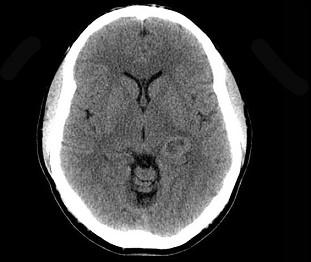

男,53岁,头晕,偏盲,请结合影像图像选择最可能的诊断()A.脑脓肿B.室管膜瘤C.脑膜炎D.脑膜瘤E.多形性恶性胶质瘤

问题 男,53岁,头晕,偏盲,请结合影像图像选择最可能的诊断()

选项 A.脑脓肿 B.室管膜瘤 C.脑膜炎 D.脑膜瘤 E.多形性恶性胶质瘤

答案 E